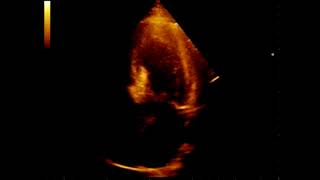

Рак матки. Новейшие методы лечения. Жить здорово! 28.02.2019